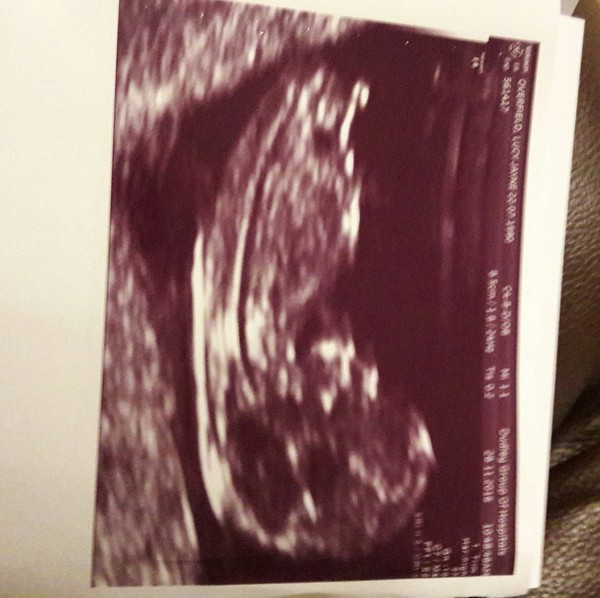

Due in June, 12 week scans happening and coming up!

VeganMama83 · 29/11/2016 08:37

Scan at 2.45pm today Shock

12+1

Hope everyone is doing ok. Had my scan yesterday! Everything is fine. There is a baby in there after all! A bit stubborn, they struggled to get the nuchal reading. He/she kept turning their back to us...

They've dated me at 11+5 so my due date is pushed to the 15th June